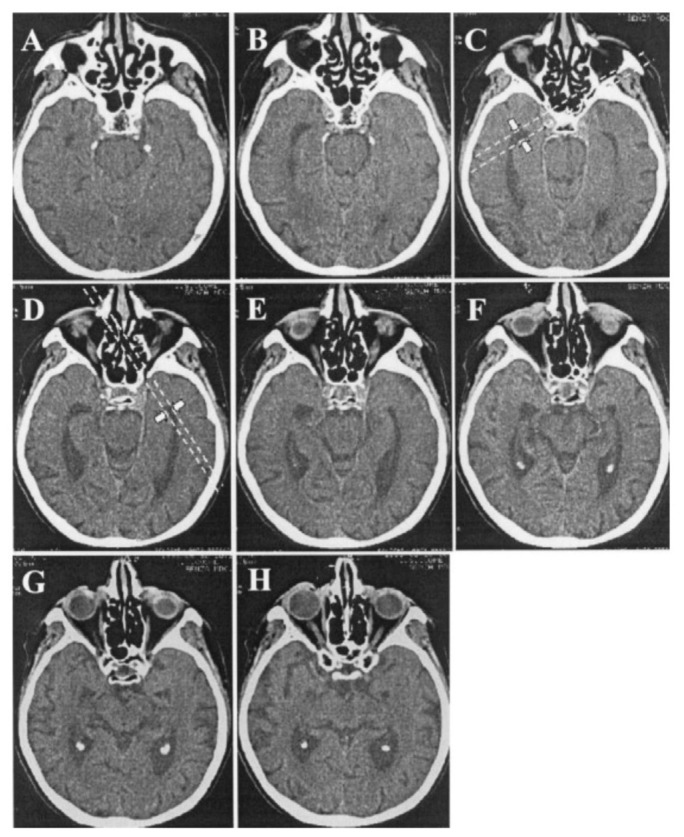

Delineating Neuroanatomical Structures for the Measurement of Temporal Horn Dilatation.